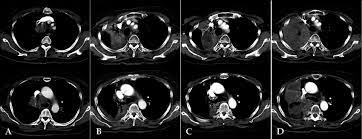

Pet Ct Scan Image Of Whole Body Comparison Axial Plane In Ct Scan And Pet Ct On The Screen For Detect Cancer Recurrence In Patient Lung Cancer Disease Stock Photo Download

Pet Ct Scan Image Of Whole Body Comparison Axial Plane In Ct Scan And Pet Ct On The Screen For Detect Cancer Recurrence In Patient Lung Cancer Disease Stock Photo Download from media.istockphoto.com

This significantly improves patients' chances of recovering from the disease and lowers related treatment costs. Thanks to advances in medical technology, a computed tomography (ct) scan now allows doctors to detect lung cancer even during its early stages. While not all detected lung nodules should be reported, radiologists. The risk of developing lung cancer due to a single ct scan of the chest is estimated to be one in 10,000. An easy ct scan can potentially detect cancer early before symptoms appear so we can start a treatment plan. Researchers expect the screening will detect lung cancer in approximately five of every 100 patients enrolled, or a five percent incidence rate that could result in over 2,000 patients potentially being diagnosed with lung cancer. When you get a ct scan, you lie on a table while a machine rotates around your. But the test is not helpful for light smokers or people who quit smoking more than 15 years ago.

It is used to look for early signs of lung cancer. After cancer treatment, a ct scan is unable to determine whether masses leftover are cancerous: Most doctors do not recommend pet/ct scans for routine follow up of patients after lung cancer treatment. A lung scan using either a ct scan or an ultrasound can detect these early signs of cancer. While it might seem obvious to assume that finding small tumors reduces one's likelihood of dying from lung cancer , this is incorrect. The risk of developing lung cancer due to a single ct scan of the chest is estimated to be one in 10,000. This can include a chest computed tomography (ct) scan and, if a nodule or mass is found, a biopsy. This significantly improves patients' chances of recovering from the disease and lowers related treatment costs. Ct scans can detect cancer at a very small size. Doctors can use a ct scan to look for lung cancer. Once a nodule is found, a workup is done to see if it is cancer. Sometimes iv contrast is administered while the images are being obtained, as this can help radiologists define certain structures and pathology. Thanks to advances in medical technology, a computed tomography (ct) scan now allows doctors to detect lung cancer even during its early stages.